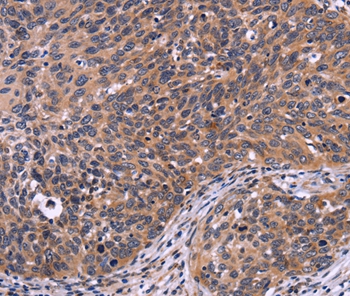

Immunohistochemical analysis of paraffin-embedded Human thyroid cancer tissue using #35942 at dilution 1/30.

Immunohistochemical analysis of paraffin-embedded Human cervical cancer tissue using #35942 at dilution 1/30.